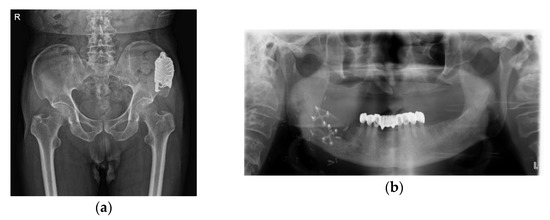

Conservative Treatment of Avulsion Fracture